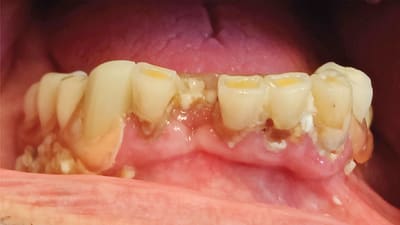

Case Report Direct Resin Restorations for Caries Treatment and Maintaining Dentition in a Patient With Dementia Gregori M. Kurtzman, DDS, MAGD, FACD, DICOI July 15, 2021 2 min read